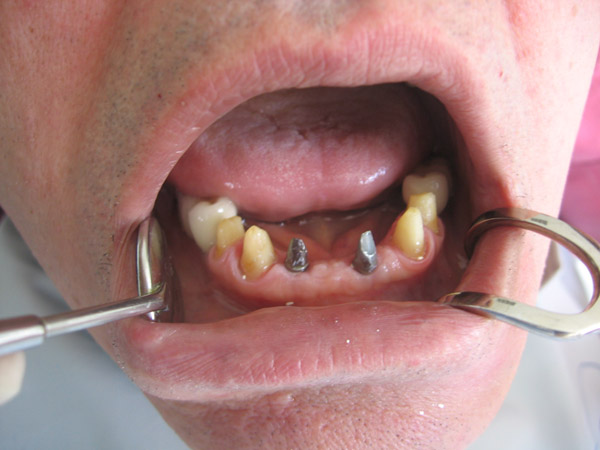

Case Studies - Dental Implants

Here you can view some of our dental implants case studies.